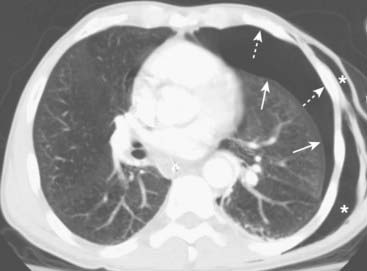

image

Figure 8-11 Bilateral pneumothoraces.

Conventional radiography is the initial modality used for detecting pneumothorax, but smaller pneumothoraces may be visible only on CT scans of the chest. This patient has bilateral pneumothoraces (solid white arrows). Air will rise to the highest point (the patient is supine in the CT scanner). Extensive subcutaneous emphysema also is present (solid black arrows); it developed because of an “air leak” from a chest tube that had been inserted earlier.